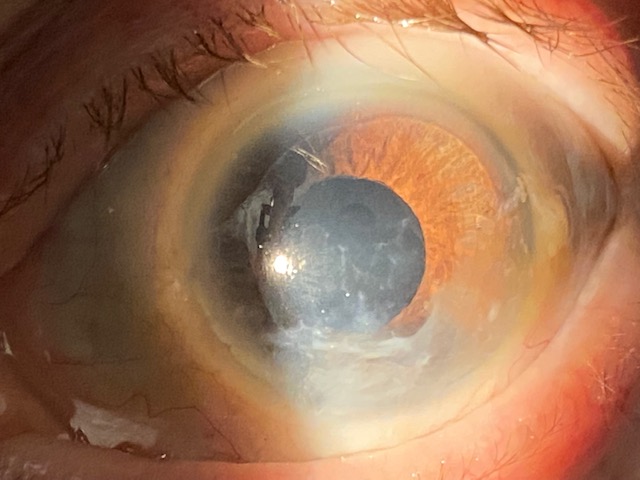

Paziente di 52 anni viene ad una visita oculistica riferendo di vedere male con l'occhio destro e di avere effettuato un intervento non meglio precisato sulla cornea negli anni '80. Non ha portato nessuna documentazione clinica.

L'obiettività oftalmologica è la seguente:

• vod: 1/50 non migliorabile con lenti;

• vos: 6-7/10 con correzione ottica;

• bod: (vedi fotografia) lenticolo opacato centro corneale di piccole dimensioni, si percepiscono nell'interfaccia cornea ospite-ospitante dei neovasi fantasma (chiusi);

• bos: cornea trasparente;

• foo: nella norma.

Effettuata una topografia corneale: cheratocono occhio sinistro. Superficie oculare nella norma.

Programmato OCT cornea e una valutazione endotelio.

Si tratta di una lamellare di piccole dimensioni opacata.

Programmato il seguente intervento chirurgico: cheratoplastica (trapianto) lamellare (DALK) con tecnica big bubble.